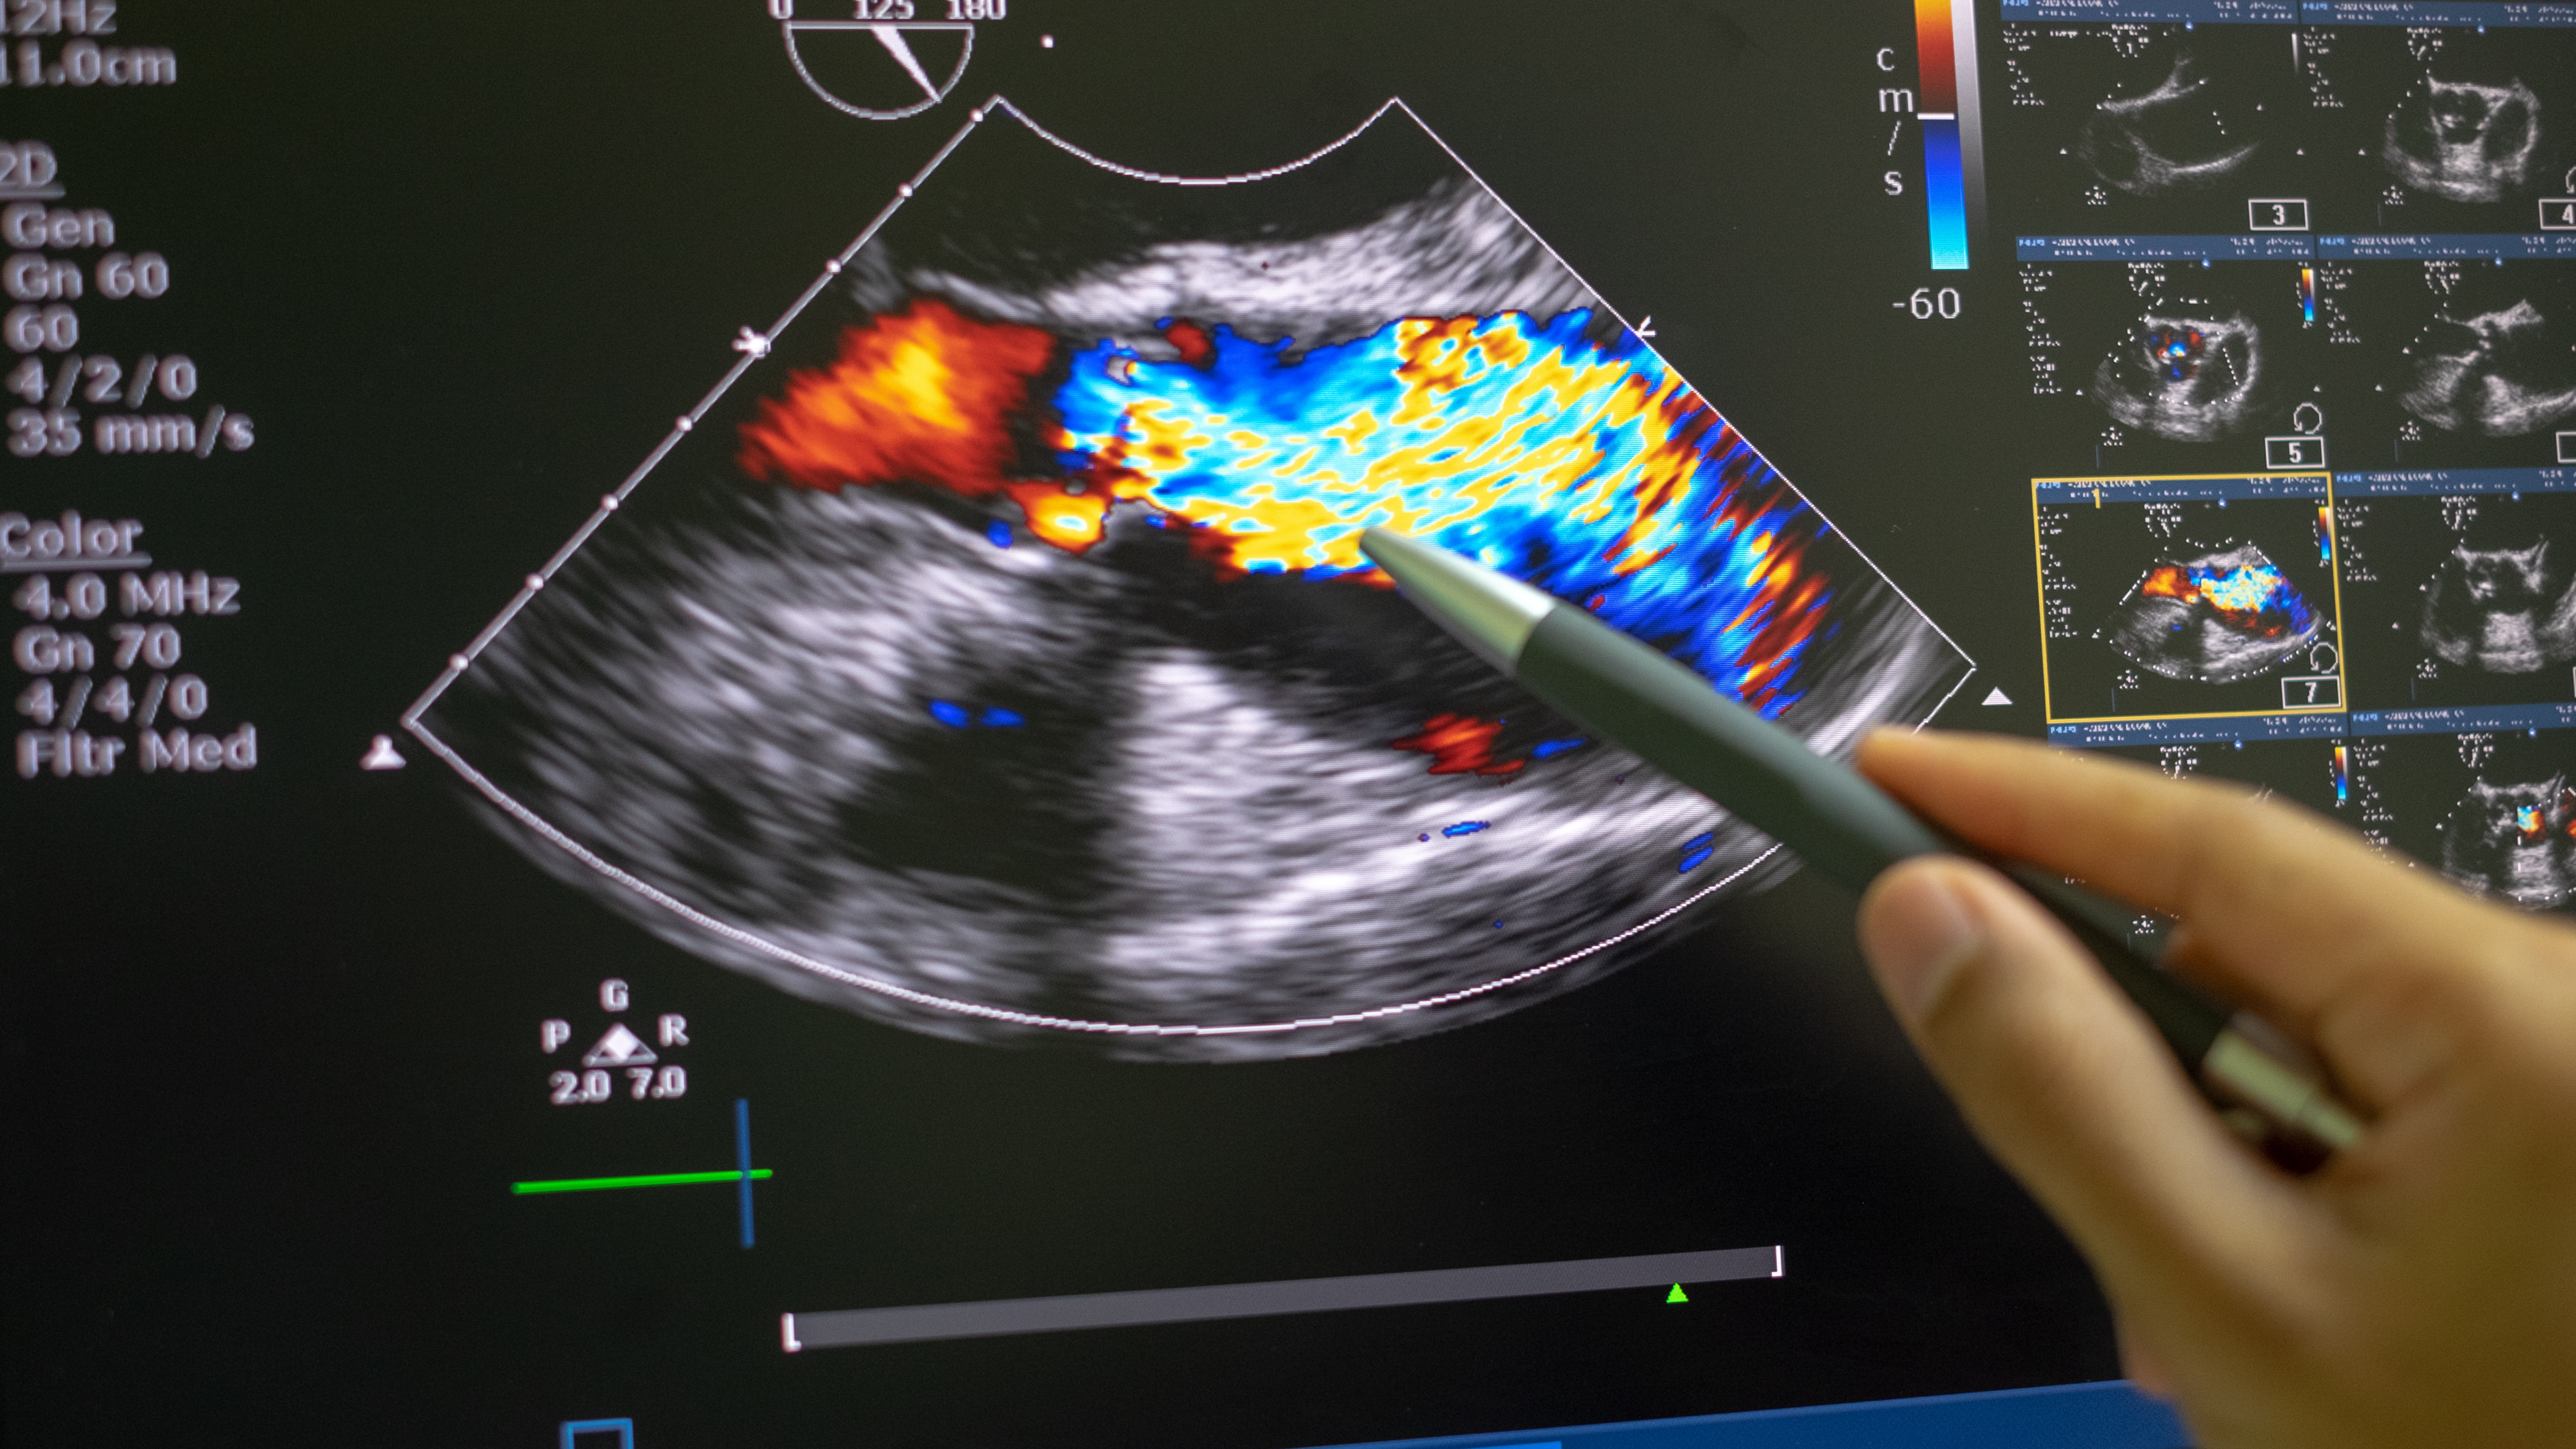

„Ach ja, die Möglichkeit besteht, ist aber sehr gering.“

01. Dezember 2022 · Zeugnisse

Als ich mit unserem zweiten Sohn schwanger war, stellte meine Frauenärztin beim Routineultraschall mehrere Fehlbildungen am Fötus fest. Die Nackenfalte, die zu …